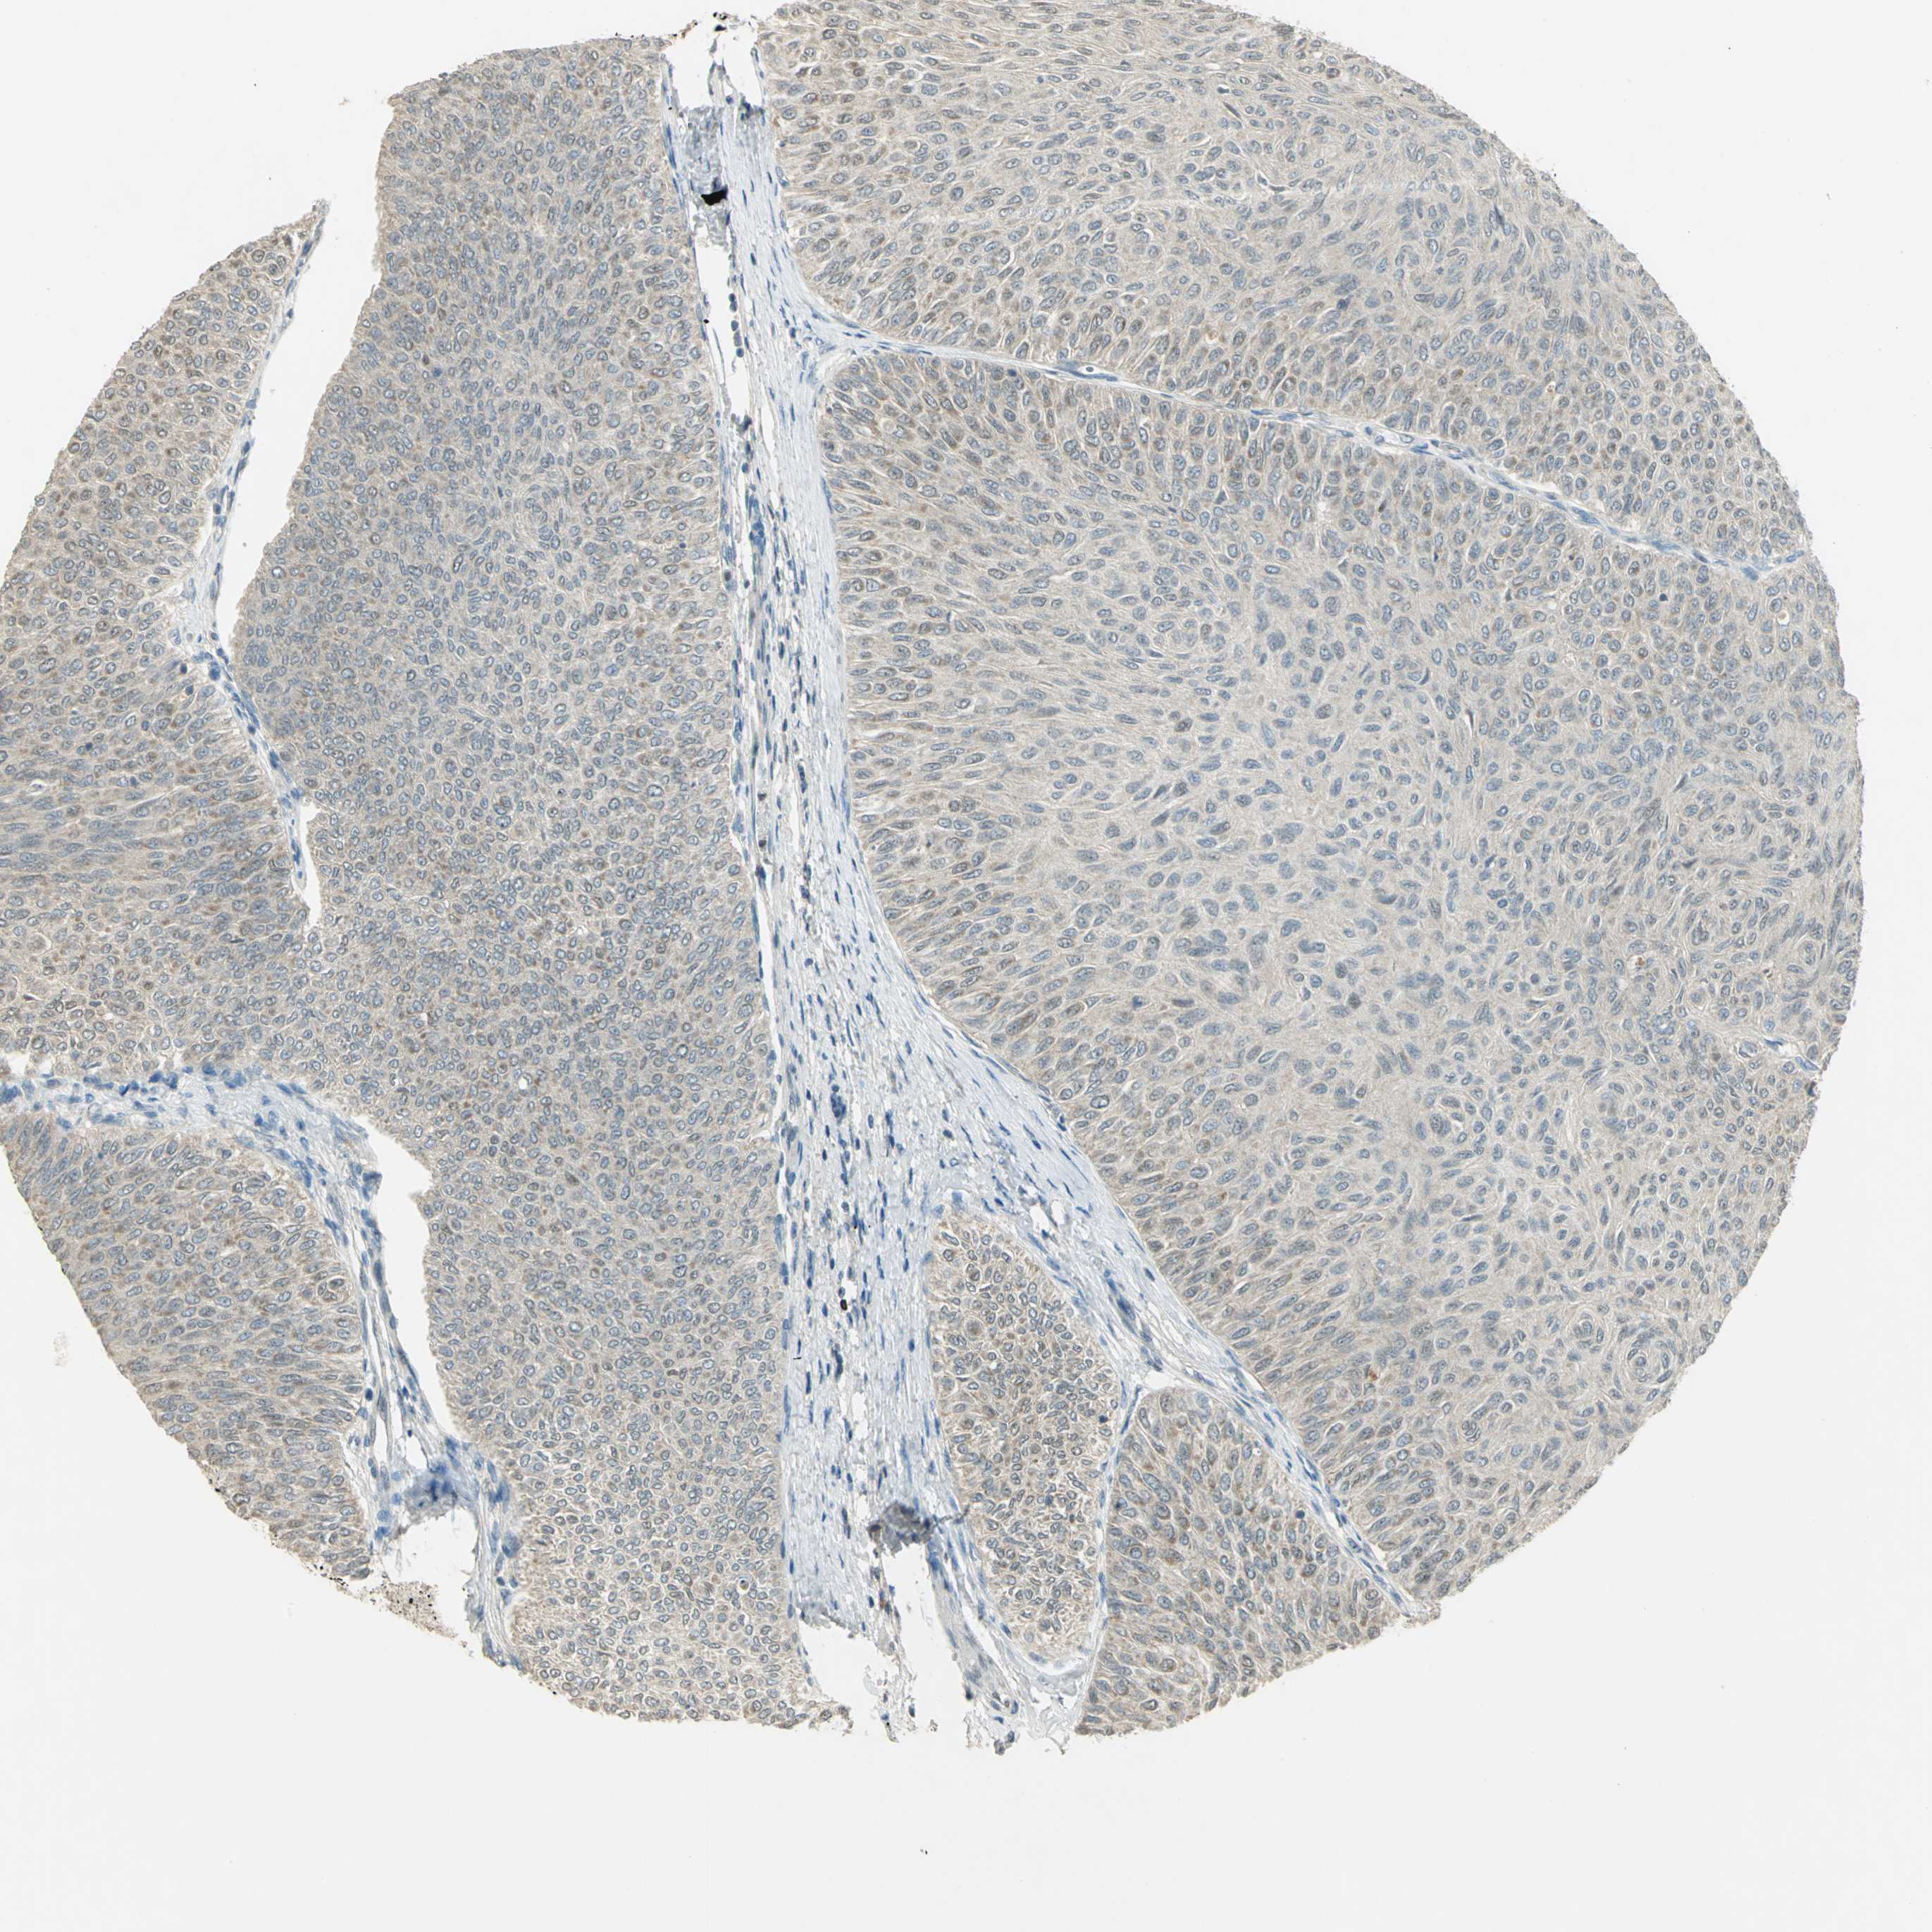

UROTHELIAL CANCER - Protein expressioni

A mouse-over function shows sample information and annotation data. Click on an image to view it in a full screen mode. Samples can be filtered based on level of antibody staining by selecting one or several of the following categories: high, medium, low and not detected. The assay and annotation is described here.

Note that samples used for immunohistochemistry by the Human Protein Atlas do not correspond to samples in the TCGA dataset.

Antibody stainingi

Antibody staining in the annotated cell types in the current human tissue is reported as not detected, low, medium, or high, based on conventional immunohistochemistry profiling in selected tissues. This score is based on the combination of the staining intensity and fraction of stained cells.

Each image is clickable and will lead to virtual microscopy that enables deeper exploration of all samples and also displays staining intensity scores, fraction scores and subcellular localization as well as patient and tissue information for each sample.

Antibody HPA005513

Antibody CAB020661

Urothelial carcinoma, High grade

Urothelial carcinoma, Low grade